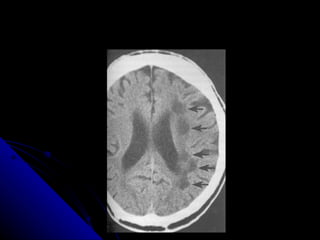

CONTROL SUBCORTICAL DEL LENGUAJE Para el lenguaje, la información fluye entre varios subsistemas Para la formulación inicial del lenguaje va desde el lóbulo frontal, opérculo frontal y la ínsula anterior Estas regiones son coordinadas por el tálamo

Estos núcleos del tálamo se conectan con regiones temporo parietales donde se hace un monitoreo semantico preverbal El tálamo es controlado por los ganglios básales El globo pálido inhibe al tálamo El caudado inhibe al globus pallidus